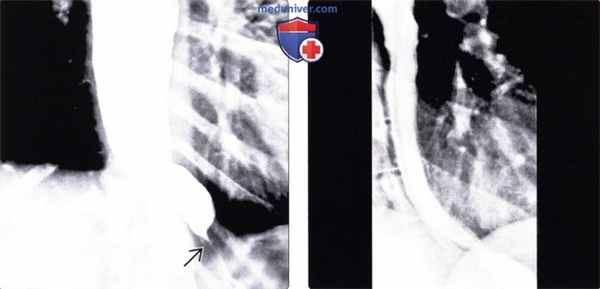

Такие снимки проводили до и после эзофагокардиомиотомии. На рентгенограммах помечали и оценивали высоту и ширину столба бариевой взвеси (на снимках горизонтальными линиями наносили верхний и нижний уровень столба бария, а стрелками по бокам его максимальную ширину, как показано на рисунке 1).

Рис. 1. Методика измерения параметров бариевого столба при ахалазии кардии

При оценке пищеводного клиренса исходили из того, что в норме у человека пищевод очищается от 200 мл бариевой взвеси через 10-20 секунд, а через 1 минуту совсем не содержит бариевого контраста. В отличие от нормы у больных с ахалазией кардии мы отметили существенную задержку бария через 1 и 5 минут исследования, зафиксированную в количественном плане по вышеуказанным параметрам бариевого столба (БС) в пищеводе.

Исходные рентгенологические данные для изучения пищеводного клиренса до и после эзофагокардиомиотомии представлены на рисунке 2.

Рис. 2. Сравнение параметров бариевого столба через 1 и 5 минут после приема контраста (до операции и через 1 месяц после эзофагокардиомиотомии)

На снимке А представлен дооперационный пищеводный клиренс у пациента со II стадией ахалазии кардии слева через 1 минуту, справа через 5 минут; Б - послеоперационный пищеводный клиренс у пациента со II стадией ахалазии кардии слева через 1 минуту, справа через 5 минут; В - дооперационный пищеводный клиренс у пациента с III стадией ахалазии кардии слева через 1 минуту, справа через 5 минут; Г - послеоперационный пищеводный клиренс у пациента с III стадией ахалазии кардии слева через 1 минуту, справа - через 5 минут.

Как видно на рис. 2, при III стадии ахалазии кардии высота столба бария была меньше, чем при II стадии ахалазии кардии, ввиду большого объема пищевода, который определяется по большей ширине дилатированного пищевода. В связи с этим при анализе мы учитывали еще и разницу в полученных данных, которая наиболее объективно и точно отражала динамику пищеводной проходимости.